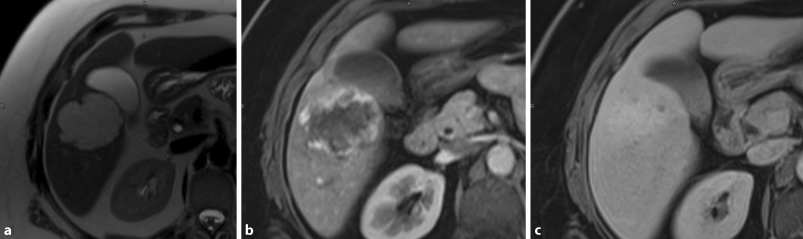

As shown in Fig. 2, the radiological diagnosis of FNH is often made on the basis of the detection of a central scar. However, this finding might be missing in half of the patients. On the other hand, a central scar may also be found in patients with fibrolamellar hepatocellular carcinoma, hepatic adenoma or intrahepatic cholangiocarcinoma. This limitation applies to all cross-sectional imaging studies. In angiography, the characteristic stellate appearance is demonstrated in only 33% of patients; moreover, FNH may even be avascular in 10% of cases. Therefore, the diagnosis of FNH is sometimes only achieved by use of several complementary imaging techniques. In patients with unclear diagnosis, a biopsy or surgical resection may be needed to achieve complete pathohistological workup. Laboratory tests are most often normal and therefore not helpful in the diagnosis. Clinical symptoms directly attributable to FNH are infrequent and therefore difficult to link to the tumour. Acute haemorrhage, necrosis or infarction are extremely rare [29]. Thus, FNH should be managed similarly to haemangiomas, with very strict indications for surgery.

Fig. 2

FNH: axial MRI in the late arterial phase (a) with Primovist® (Bayer Schering Pharma, Berlin, Germany) shows a large, slightly hyperintense lesion (arrow), with a hypodense centre, in the right liver, consistent with a central scar (arrowhead) [9]. The hepatobiliary phase (b) images show a strong uptake of Primovist, which is a typical sign of FNH